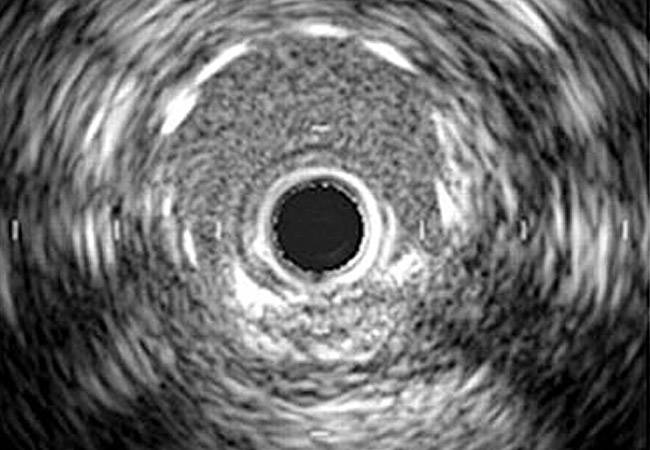

¿Qué es la Ecografía Intravascular (IVUS)?

La Ecografía Intravascular (IVUS) es una técnica diagnóstica para monitorizar el estado de una arteria coronaria a través de imágenes recogidas con una sonda de Ultrasonidos. Es especialmente adecuada para evaluar el estado del vaso sanguíneo, las posibles placas de Arterioesclerosis y si un Stent se ha insertado correctamente.

La Ecografía Intravascular (IVUS) se realiza mediante una sonda ultrasónica insertada en un Catéter que se introduce en las arterias coronarias hasta el punto afectado. La sonda emite los Ultrasonidos, que alcanzan el vaso y luego son recogidos por la máquina, donde se procesan en imágenes.

El sonido intravascular brinda imágenes con excelente resolución, por lo que posibilita medir la gravedad de las lesiones. En este sentido, los resultados son de gran ayuda para los especialistas, ya que aportan información necesaria para evaluar la composición de la placa, la ubicación dentro de la pared vascular y la posibilidad de la existencia de Reestenosis y Trombosis.

La aplicación del IVUS permite detectar la presencia de placa en las arterias, evaluar el grado de angostamiento de los vasos sanguíneos, diagnostica la existencia de estenosis, posibilita la aplicación de un Stent más precisa y evita la incidencia de Trombosis.